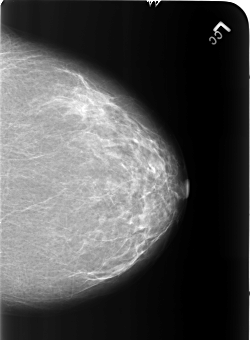

LEFT_CC LINES 5440 PIXELS_PER_LINE 4000 BITS_PER_PIXEL 12 RESOLUTION 50 NON_OVERLAY